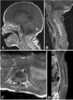

Intramedullary mass

Spinal tumors are neoplasms located in either the vertebral column or the spinal cord. There are three main types of spinal tumors classified based on their location: extradural and intradural (intradural-intramedullary and intradural-extramedullary). [Source: Wikipedia ]